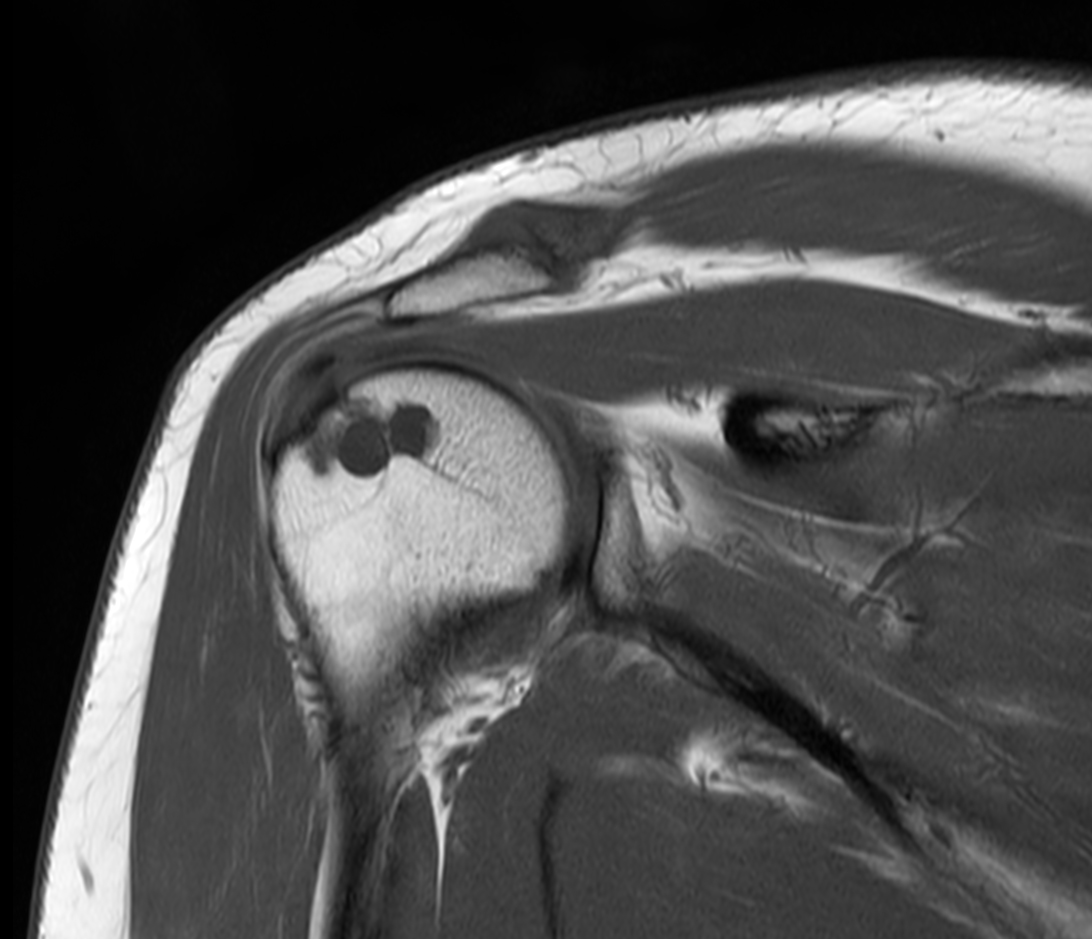

Coronal PDw TSE